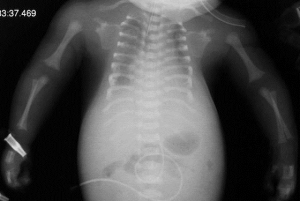

Displasia Espondilo Epifisária é uma designação que descreve as manifestações primárias radiológicas como alterações de coluna (‘espondilo‘) e das epífises (displasia óssea nas extremidades). Há

É uma desordem rara, um distúrbio específico e multissistêmico. O termo “Distrofia Torácica Asfixiante” tem sido utilizado tanto como sinônimo de Síndrome de Jeune quanto,

A Displasia Diastrófica origina-se em uma alteração do gene que resulta em mudanças da matriz extracelular. É sempre uma doença autossômica recessiva. Quanto a outras

Displasia Espondilo Epifisária Tardia (DEET) é rara, afetando cerca de um em cada 150 mil indivíduos. É uma desordem recessiva ligada ao cromossomo X. Isso

Kniest é uma displasia óssea pouco frequente, particularmente caracterizada pela rigidez progressiva e alargamento de várias articulações. Além disso, compartilha muitos outros riscos médicos com